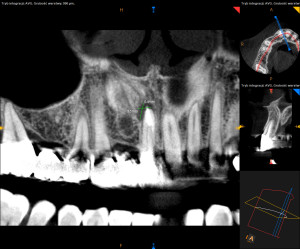

Dokumentacja RTG

- CBCT przed i po zabiegu